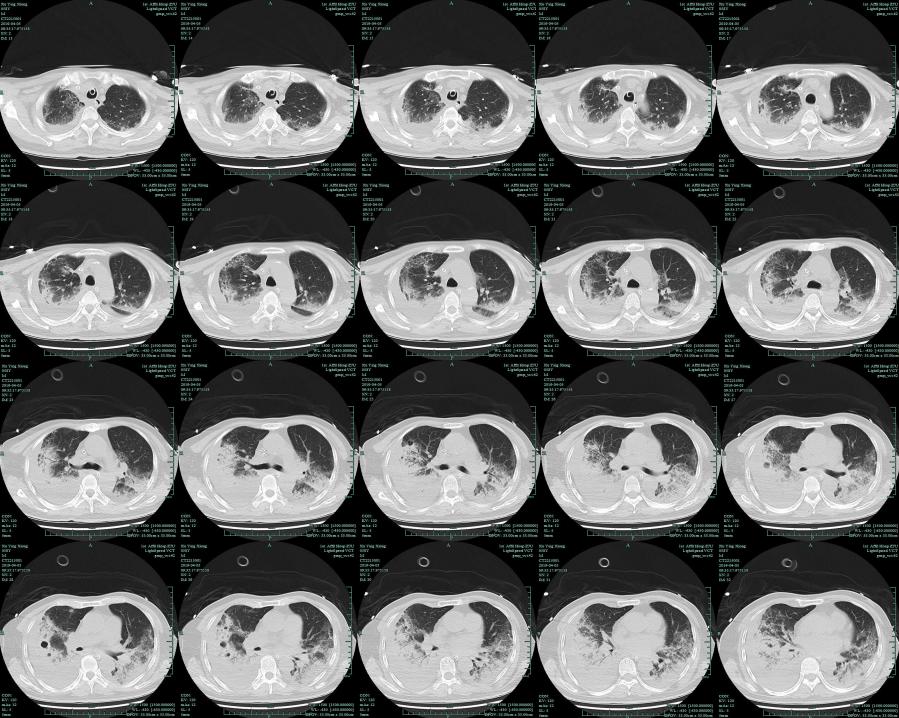

入院后肺部CT提示双肺弥漫性病变。这个病人是不是重症社区获得性肺炎?

/入院后肺部CT/